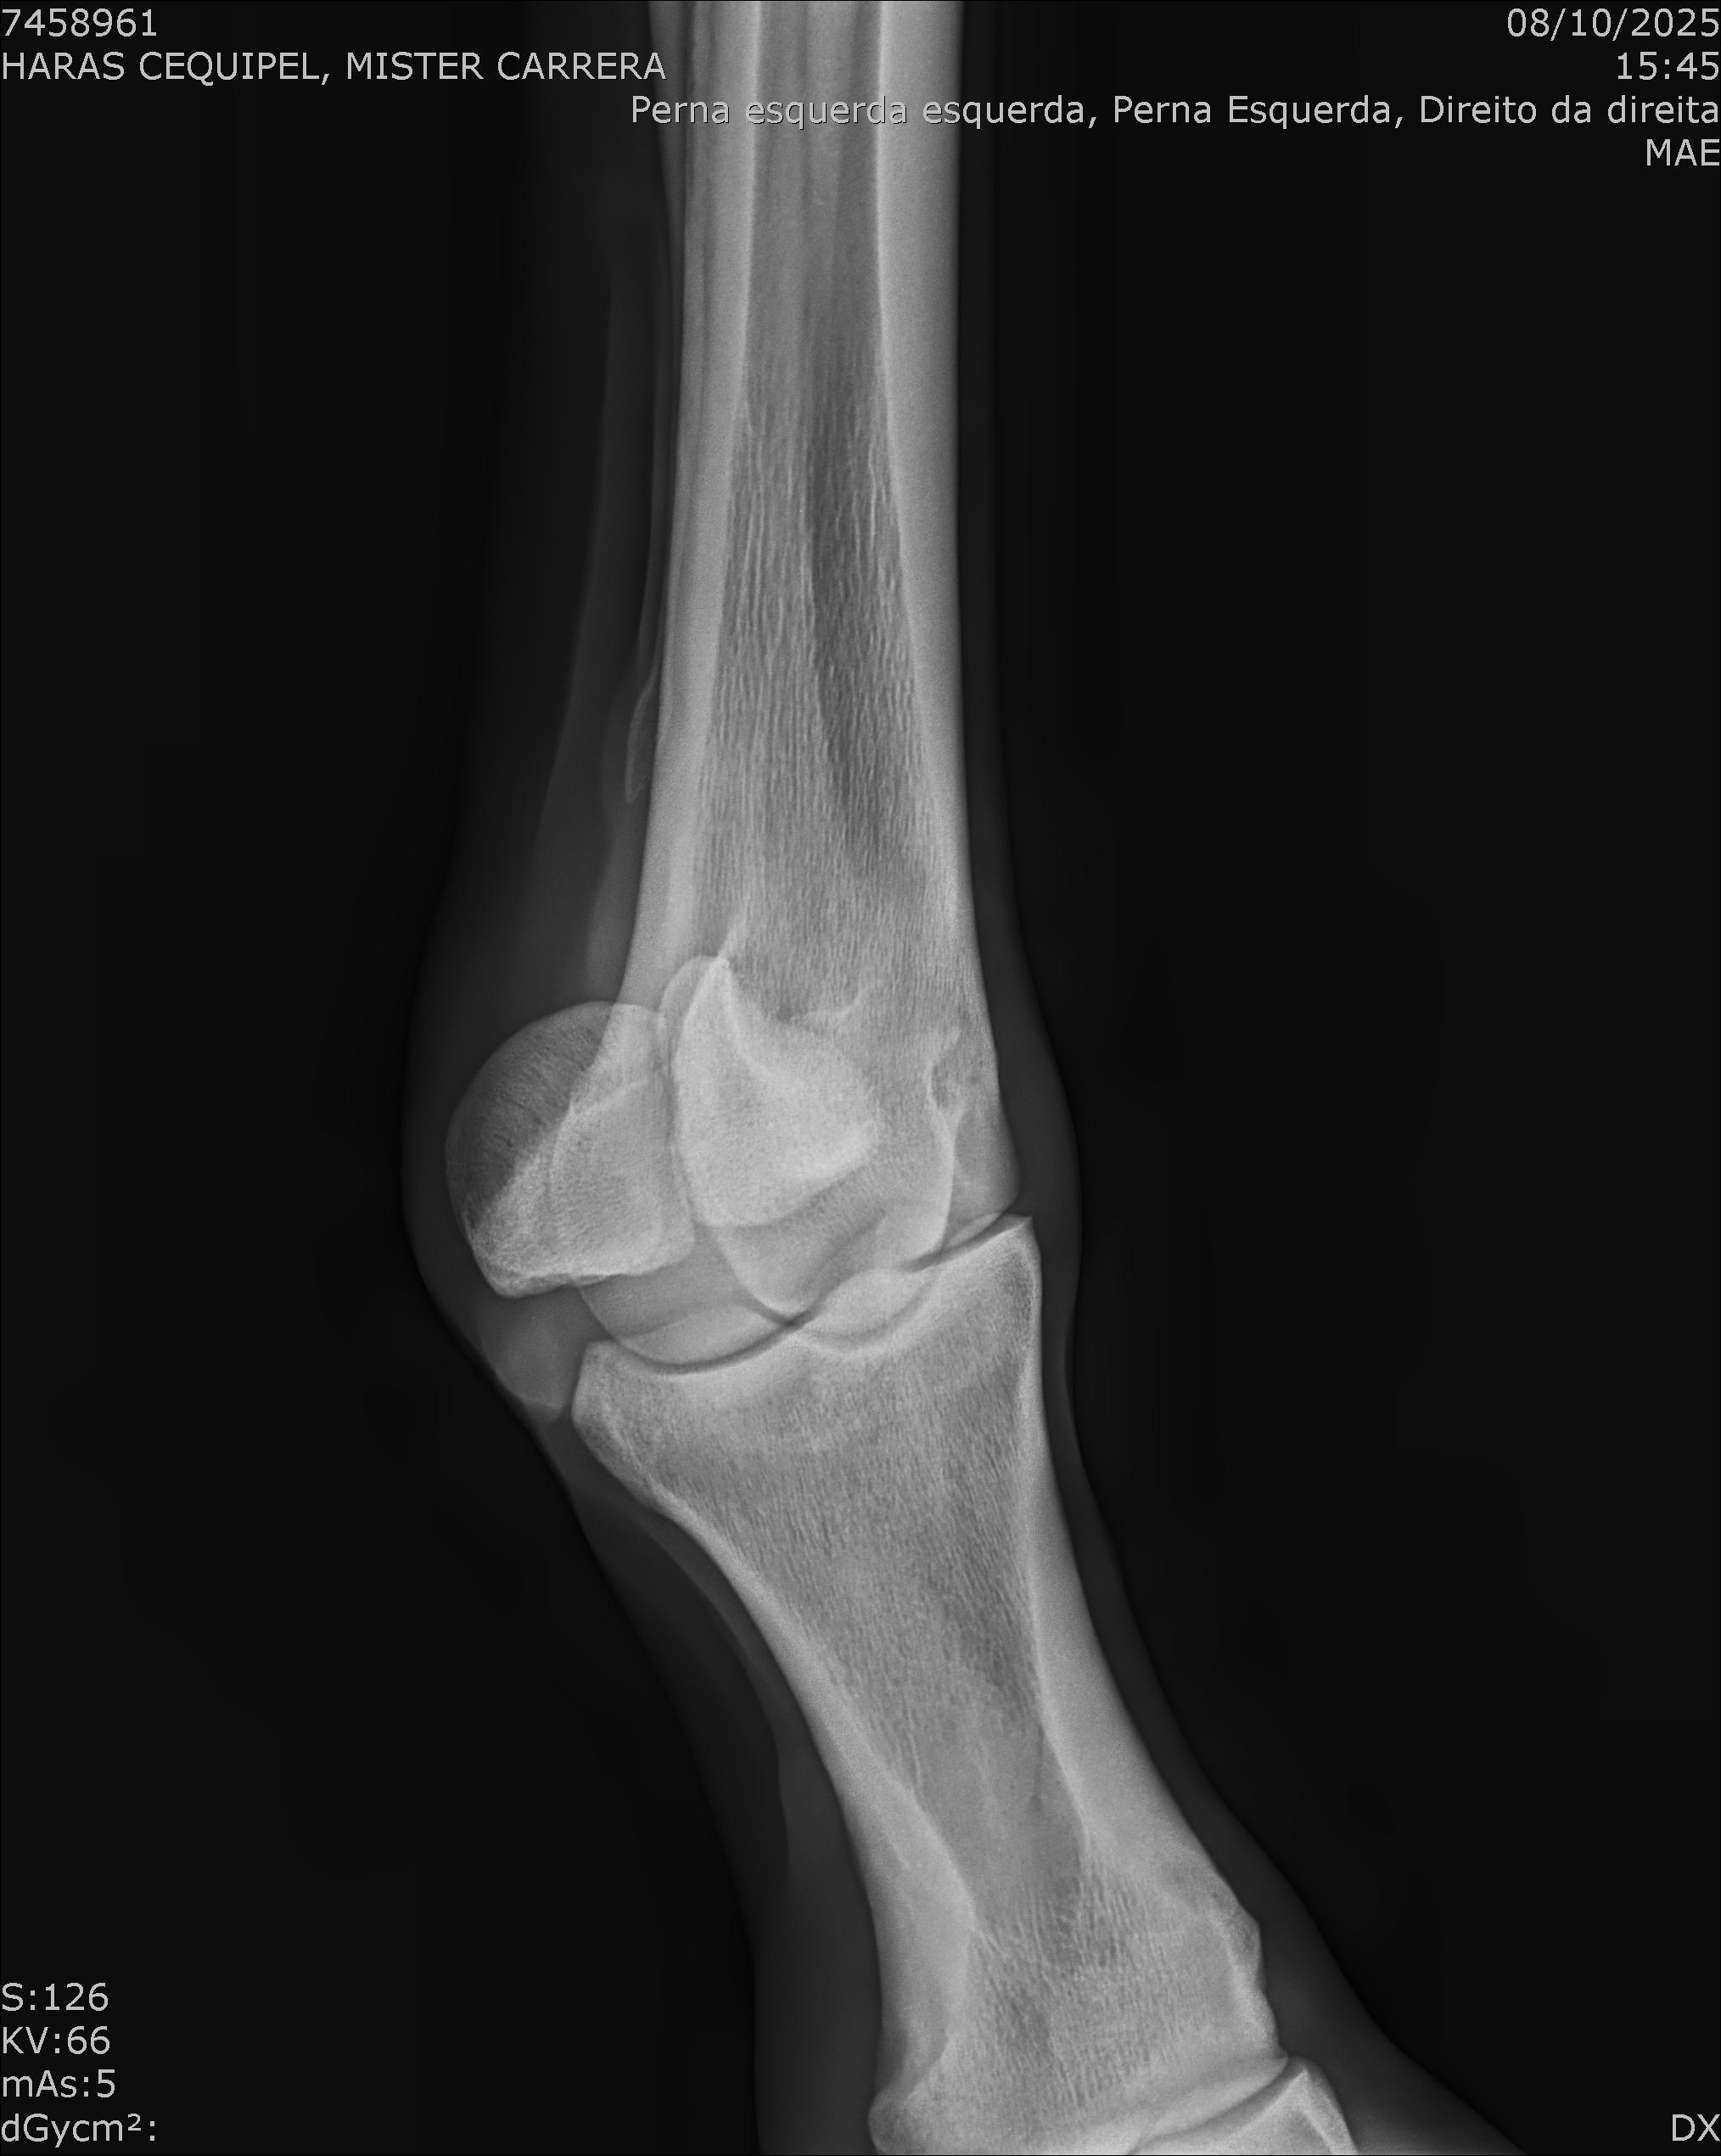

:: RAIOS-X DO LOTE